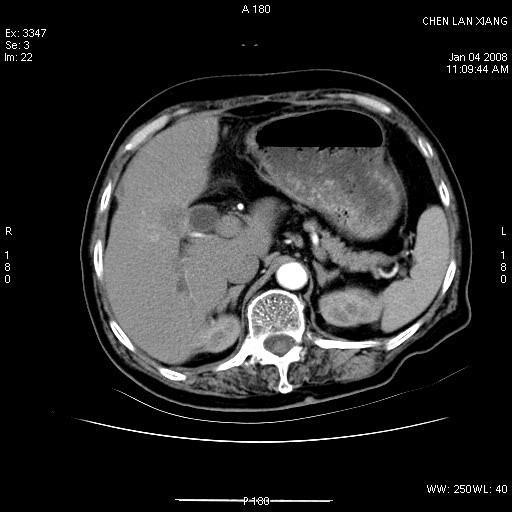

女,76岁,腹痛3-4天,b超示:肝内实性肿物,胆囊强回声,胆总管扩张.

考虑:1、胆总管下端结石伴梗阻性肝内外胆管扩张(肝左叶外侧段肝内胆管多发结石、胆管炎);

2、肿囊癌累及肝,不除外 黄色肉芽肿性胆囊炎。

1 胆总管末端结石伴肝内胆管结石,肝内外胆管扩张。2 胆囊扩大,胆囊壁不规则增厚,内见软组织密度影。考虑:慢性胆囊炎,不除外胆囊癌!

ct所见:1、 肝内胆管结石,肝内外胆管扩张。低位胆道梗阻,胆总管下端结石;2 胆囊扩大,胆囊壁不规则增厚

考虑:胆总管下端结石并肝内外胆管扩张,肝内胆管结石;

慢性胆囊炎

标题: 肝右叶病灶

胆囊癌侵犯肝右叶?

1)胆囊癌伴肝脏转移。2)胆总管下端结石、肝内胆管结石伴肝内外胆管扩张。